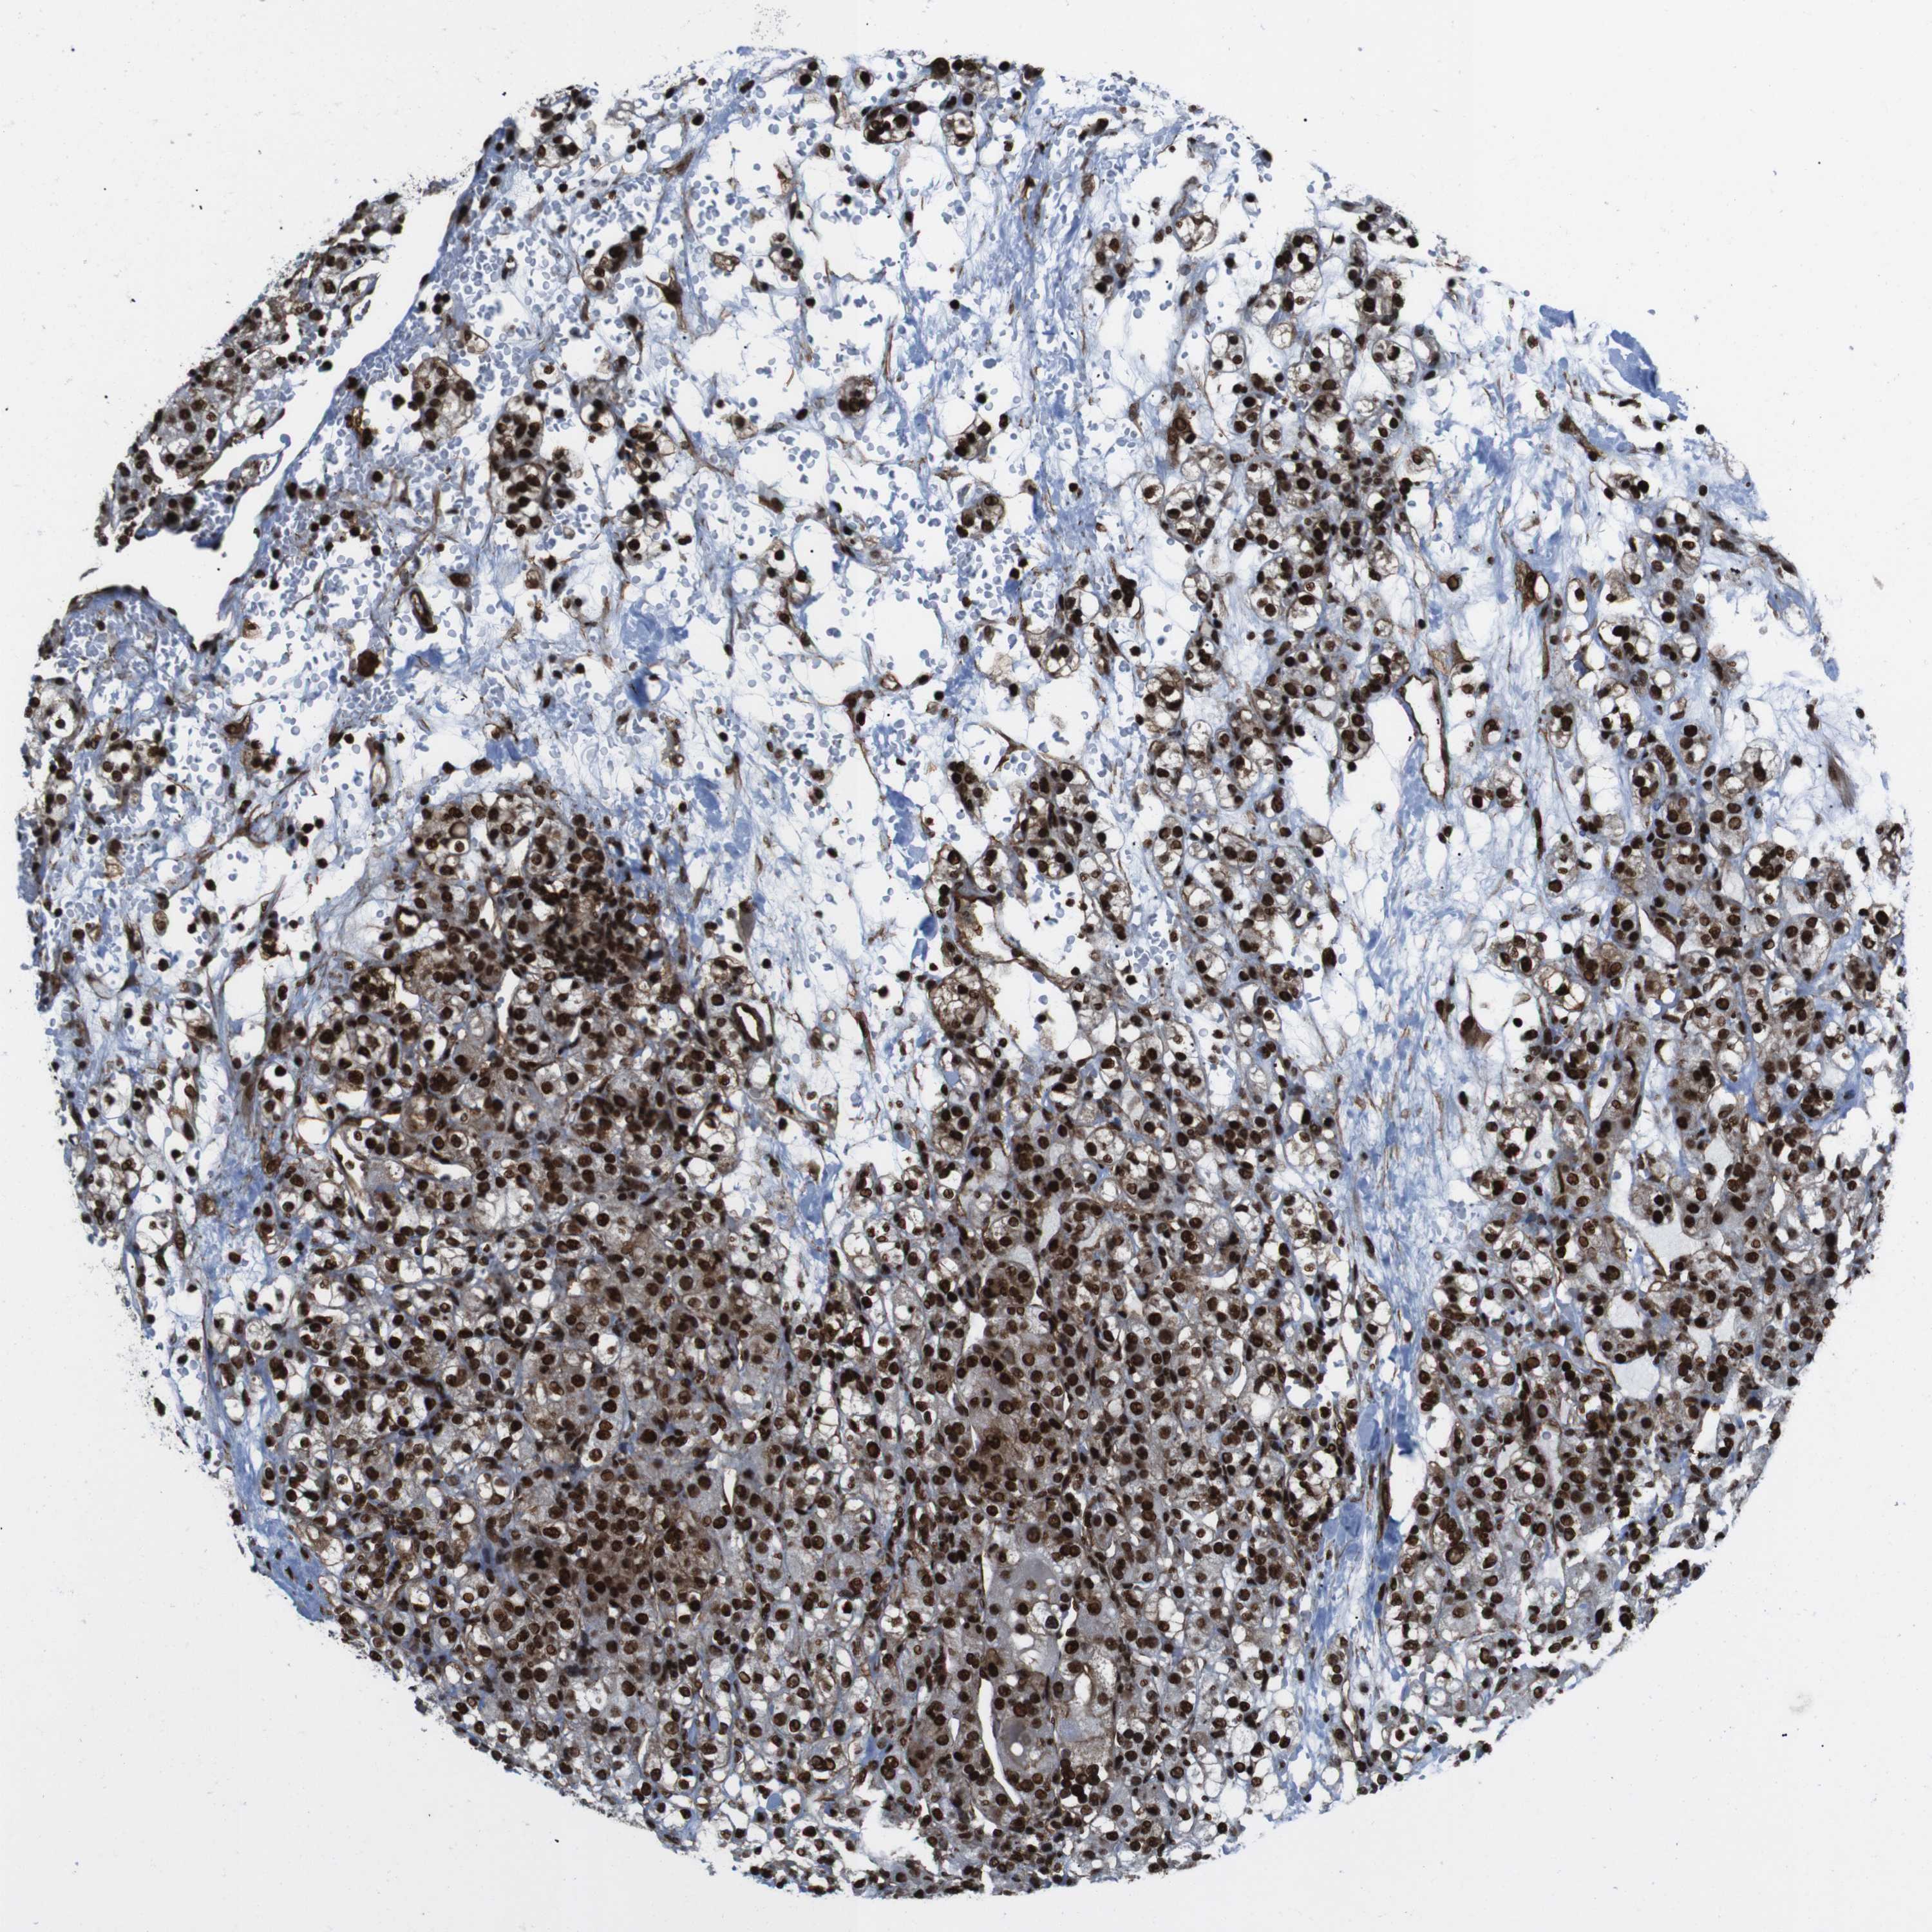

KIDNEY RENAL CLEAR CELL CARCINOMA (TCGA) - Interactive survival scatter ploti

The Survival Scatter plot shows the clinical status (i.e. dead or alive) for all individuals in the patient cohort, based on the same data that underlies the corresponding Kaplan-Meier plots. Patients that are alive at last time for follow-up are shown in blue and patients who have died during the study are shown in red.

The x-axis shows the expression levels (FPKM) of the investigated gene in the tumor tissue at the time of diagnosis. The y-axis shows the follow-up time after diagnosis (years). Both axes are complimented with kernel density curves demonstrating the data density over the axes. The top density plot shows the expression levels (FPKM) distribution among dead (red) and alive patients (blue). The right density plot shows the data density of the survived years of dead patients with high and low expression levels respectively, stratified using the cutoff indicated by the vertical dashed line through the Survival Scatter plot. This cutoff is automatically defined based on the FPKM cutoff that minimizes the p-score. The cutoff can be changed by dragging the vertical line or by entering a cutoff value in the square labeled "Current cut-off".

Under the Survival Scatter plot the p-score landscape (black curve; left axis) is shown together with dead median separation (red curve; right axis). Dead median separation is the difference in median mRNA expression between patients who have died with high and low expression, respectively. It is calculated as follows: median FPKM expression of dead patients with high expression - median FPKM expression of dead patients with low expression. This is intended to aid the user in visually exploring custom cutoffs and the associated p-scores and dead median separation.

Individual patient data is displayed and can be filtered by clicking on one or more of the category buttons on the top of the page. Categories describing expression level and patient information include: high, low, alive, dead, female, male and tumor stages. The scale of the x-axis can be toggled between linear and log-scale by clicking on the "x log" button. Mouse-over function shows TCGA ID, patient information and mRNA expression (FPKM) for each patient.

& Survival analysisi

Kaplan-Meier plots summarize results from analysis of correlation between mRNA expression level and patient survival. Patients were divided based on level of expression into one of the two groups "low" (under cut off) or "high" (over cut off). X-axis shows time for survival (years) and y-axis shows the probability of survival, where 1.0 corresponds to 100 percent.

HNRNPU is potential prognostic, high expression is favorable in Kidney Renal Clear Cell Carcinoma (TCGA)

Best expression cut offi

Based on the FPKM value of each gene, patients were classified into two groups and association between prognosis (survival) and gene expression (FPKM) was examined. The best expression cut-off refers the FPKM value that yields maximal difference with regard to survival between the two groups at the lowest log-rank P-value. Best expression cut-off was selected based on survival analysis .

When clicking on this number, the vertical dashed line indicating cut-off, the interactive survival plot, and the Kaplan-Meier curve will be adjusted to show results based on the best expression cut-off.

: 166.47

Median expressioni

Median expression refers to the median FPKM value calculated based on the gene expression (FPKM) data from all patients in this dataset. When clicking on this number, the vertical dashed line indicating cut-off, the interactive survival plot, and the Kaplan-Meier curve will be adjusted to show results based on the median expression.

: N/A

Median follow up timei

Median follow up time refers to the median time (years) after diagnosis with this type of cancer, based on clinical data from all patients in this dataset.

P scorei

Log-rank P value for Kaplan-Meier plot showing results from analysis of correlation between mRNA expression level and patient survival.

N/A

5-year survival highi

5-year survival for patients with higher expression than the expression cutoff.

For melanoma and glioma, 3-year survival is shown.

5-year survival lowi

5-year survival for patients with lower expression than the expression cutoff.

TCGA RNA samplesi

RNA-seq data is reported as average FPKM (number Fragments Per Kilobase of exon per Million reads), generated by the The Cancer Genome Atlas (TCGA) .

Normal distribution across the dataset is visualized with box plots, shown as median and 25th and 75th percentiles. Points are displayed as outliers if they are above or below 1.5 times the interquartile range. FPKM values of the individual samples are presented next to the box plot.

Average pTPM 137.9

Number of samples 521